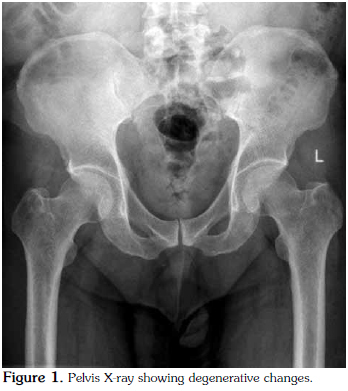

The bilateral knee radiographs of the patient were normal (Figure 2), but those of the feet revealed osteodegenerative changes (Figure 3) and bilateral heel spurs (Figure 4).